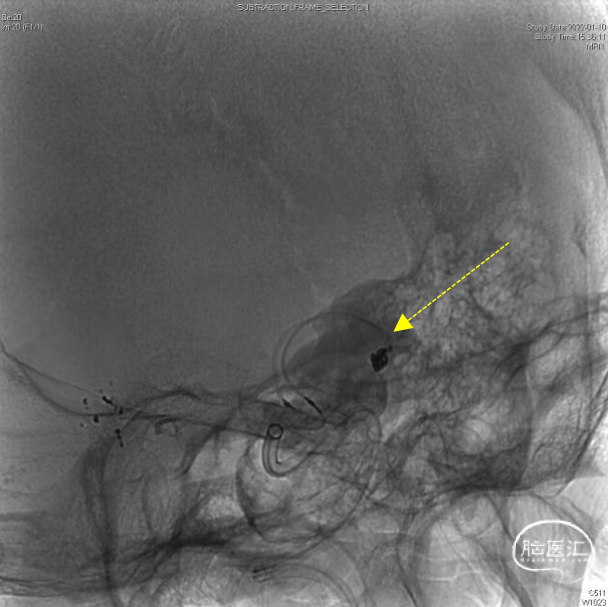

造影显示:颈内动脉迂曲,动脉瘤大小3.9×2.2mm,动脉瘤侧壁有边支发出,远端延续为较粗的向颞叶供血动脉(红色虚线)。

6F通桥银蛇DA远端通路导引导管到位后,工作角度微导管抵近造影,证实动脉瘤侧壁发出的边支向颞叶供血。

微导管送入弹簧圈 3mm×4cm,意向性栓塞。空出侧壁的边支动脉起始部。同时使用另一条微导管在远离边支的瘤颈部填(弹簧圈1mm×2cm)。

动脉瘤大部填塞后,边支动脉血流完好。